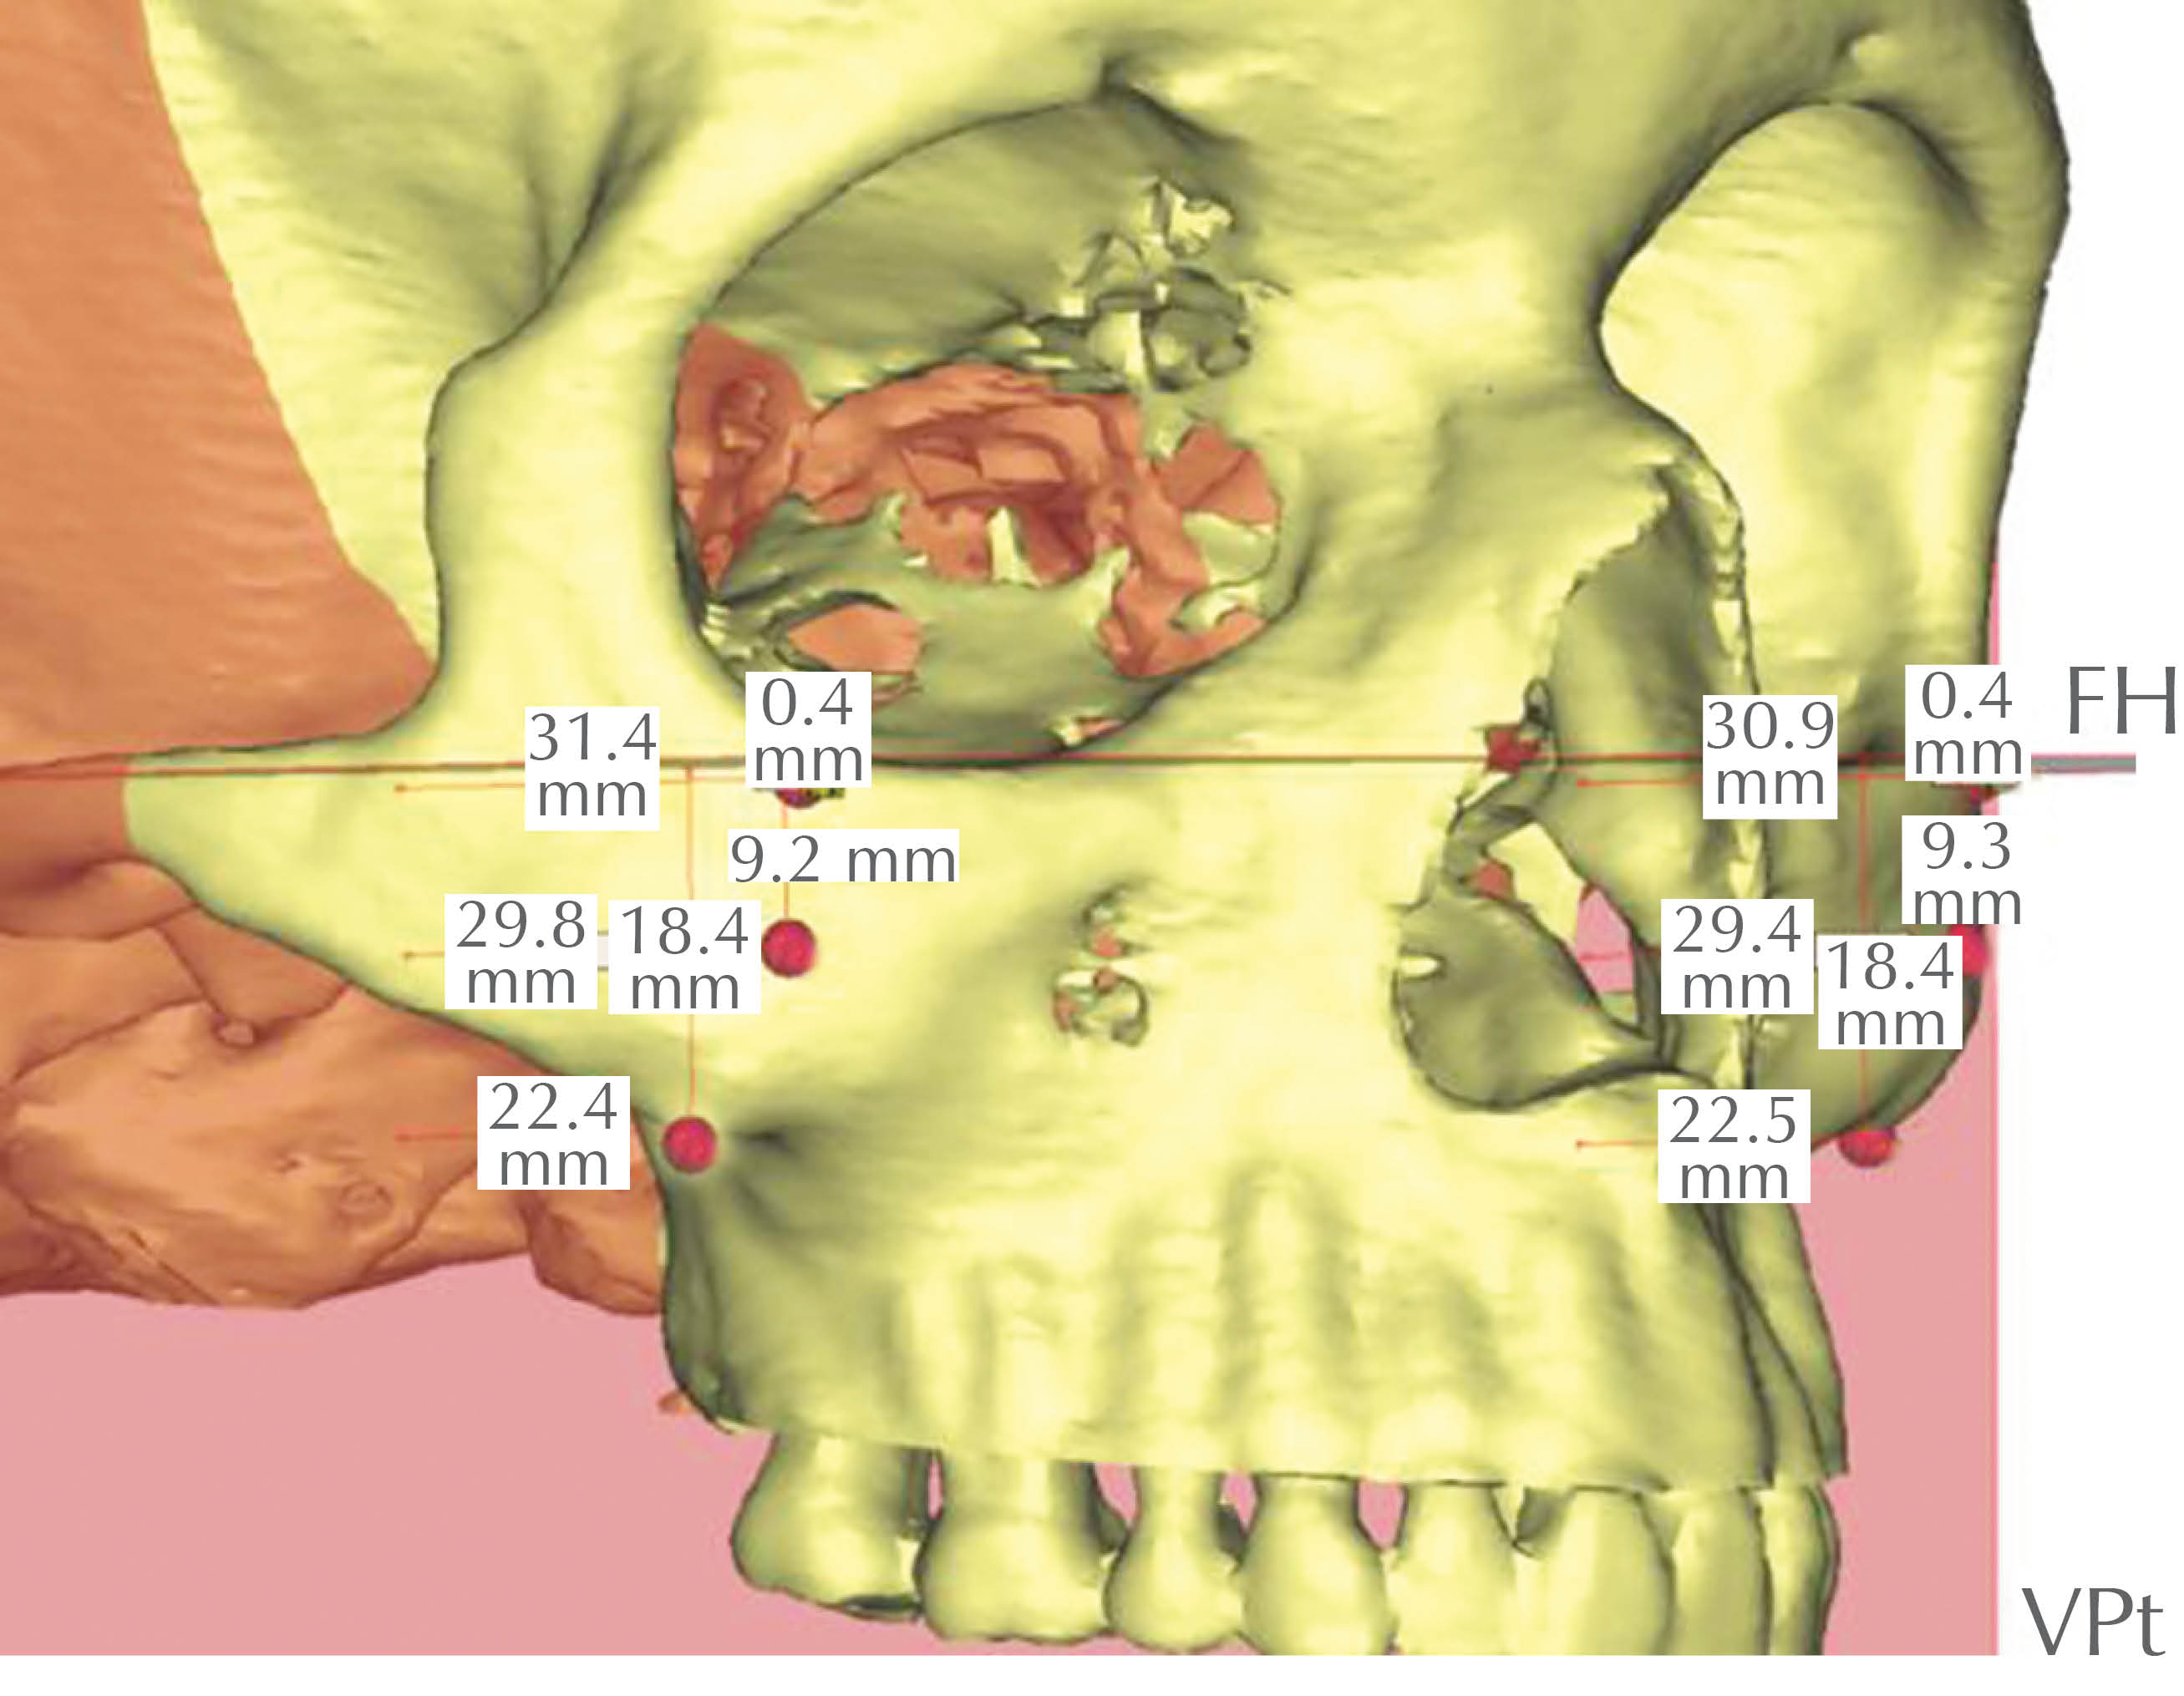

• 34. PMS-VPt: proyección anteroposterior de la prominencia malar superior (PMS); distancia de la PMS a la vertical pterigoidea (VPt) (Figura 39).

• 35. PMS-FH: ubicación vertical de la prominencia malar superior (PMS); distancia de la PMS al plano horizontal de Frankfurt (FH) (Figura 39).

• 36. PMM-VPt: proyección antero-posterior de la prominencia malar media (PMM); distancia de la PMM a la vertical pterigoidea (VPt) (Figura 39).

• 37. PMM-FH: ubicación vertical de la prominencia malar media (PMM); distancia entre la PMM y el plano horizontal de Frankfurt (FH) (Figura 39).

• 38. PMI-VPt: proyección anteroposterior de la prominencia malar inferior (PMI); distancia de la PMI a la vertical pterigoidea (VPt) (Figura 39).

• 39. PMI-FH: ubicación vertical de la prominencia malar inferior (PMI); distancia de la PMI al plano horizontal de Frankfurt (FH) (Figura 39).

Figura 39